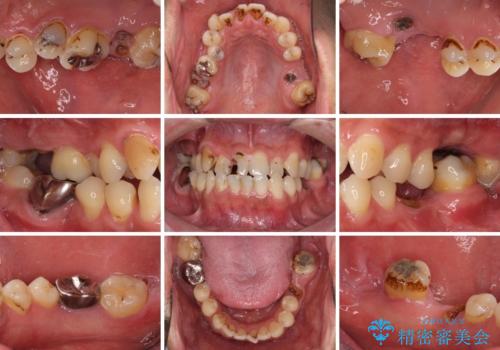

- 前歯や奥歯の虫歯を放置しており、それらの治療を契機に真っ白な歯にしたいとのことで来院された患者様です。

咬み合わせを改善するに当たって、抜歯しなければならない歯や歯列の改善が必要な箇所があったため、矯正治療やインプラント治療から始めていくこととしました。

不自然なくらい真っ白にしたいとのことでしたので、透明感のないフルジルコニアクラウンを用いて補綴することとしました。